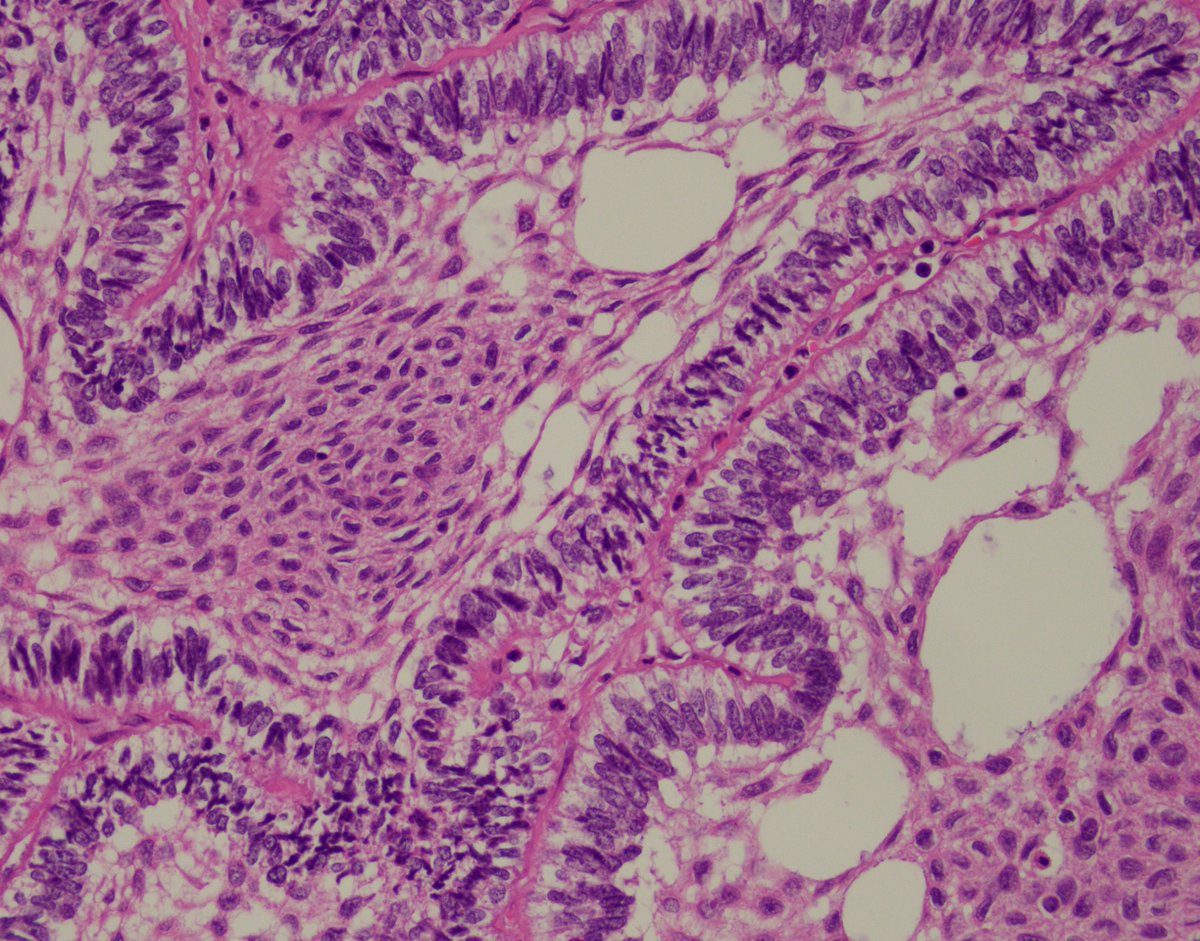

Cristina Magi-Galluzzi, M.D., Ph.D., Robert and Ruth Anderson Endowed Chair in Pathology, was installed as the 2026-2027 president of USCAP - United States and Canadian Academy of Pathology @TheUSCAP, effective April 1, 2026. Congratulations, Dr. Magi! 💚 bit.ly/4sgU4D1